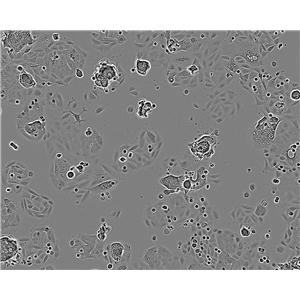

背景信息:该细胞是由Liebovitz A等于1986年从一名43岁的白人女性乳腺导管癌患者的乳腺切除肿瘤组织中分离建立的;手术前该病人曾接受过广泛的化疗。该细胞HER-2/neu癌基因序列有15倍的扩增;雌激素受体ER、孕激素受体PR和糖蛋白P阴性。